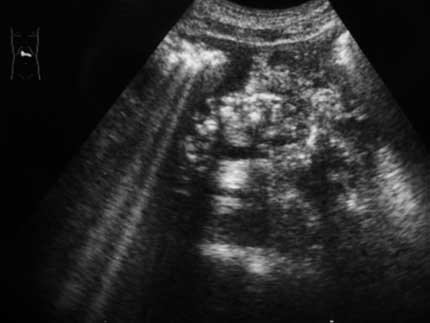

Хронический калькулезный панкреатит, только без кисты (может вместе праздновали

)

- IMG_6889w.jpg (12.38 КБ) 1489 просмотров